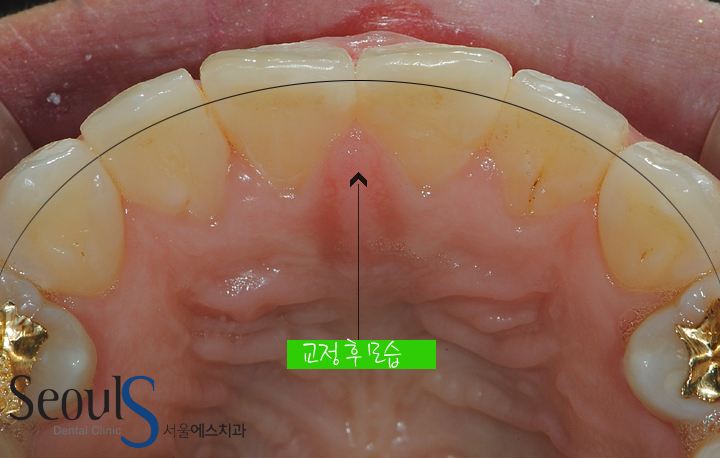

교정 후 모습입니다

치아가 가지런하게 개선된 모습입니다

교정 전후 앞니 모습입니다

삐뚤었던 앞니가 교정후 가지런해진 모습입니다